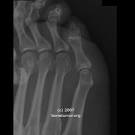

Radiográficamente la lesión tiene su epicentro en la región de la superficie cortical externa del hueso. No hay tallo o pedúnculo como en un osteocondroma. La localización más frecuente es adyacente a la metáfisis. La corteza también pueden intervenir en un grado variable, pero las lesiones no implican el espacio medular. Hay una masa fuera de los confines del hueso que contiene la osificación amorfo. En los casos de esta lesión que he visto que no había anillo y las cifras de arco visto en la matriz osificada, y tampoco hubo ningún rastro de la organización trabecular del material osificado.

No hay reacción perióstica, pero la lesión puede levantar el periostio y crear "columnas" o "contrafuertes" del periostio maduros en cada extremo de la masa que parecen proyectarse desde el eje del hueso. La presión de crecimiento de la lesión puede crear una forma de platillo o complejo defecto de forma en el hueso subyacente. Un examen de laboratorio sólo ayudan a confirmar que no existe una enfermedad sistémica, como la infección. La Gammagrafía ósea mostrará que la lesión está activamente haciendo hueso, y sólo es útil para contar las lesiones. TC muestra una imagen más precisa de la lesión y su localización yuxtacortical. Se puede poner de manifiesto el carácter amorfo de la materia de osificación dentro de la lesión, así como ayudar a distinguir el tumor de osteocondroma, osteoma osteoide, y la miositis osificante, pero no de osteosarcoma perióstico y osteosarcoma parosteal.